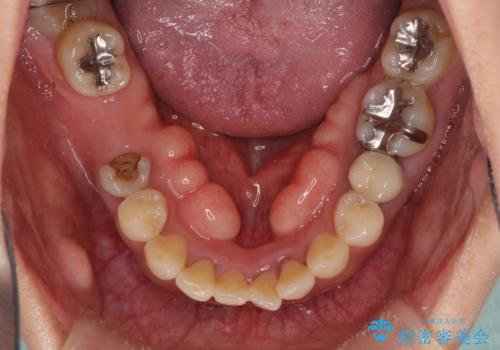

- 右下の欠損部の治療を希望して来院された患者様です。

部分矯正を行った後にインプラント埋入と手前の歯の根管治療を行い、その後補綴治療を行うこととしました。

治療途中より、上の歯や反対側の銀歯、上顎前歯の色合いや下顎前歯のデコボコが気になってきたため、全てを治療することとしました。